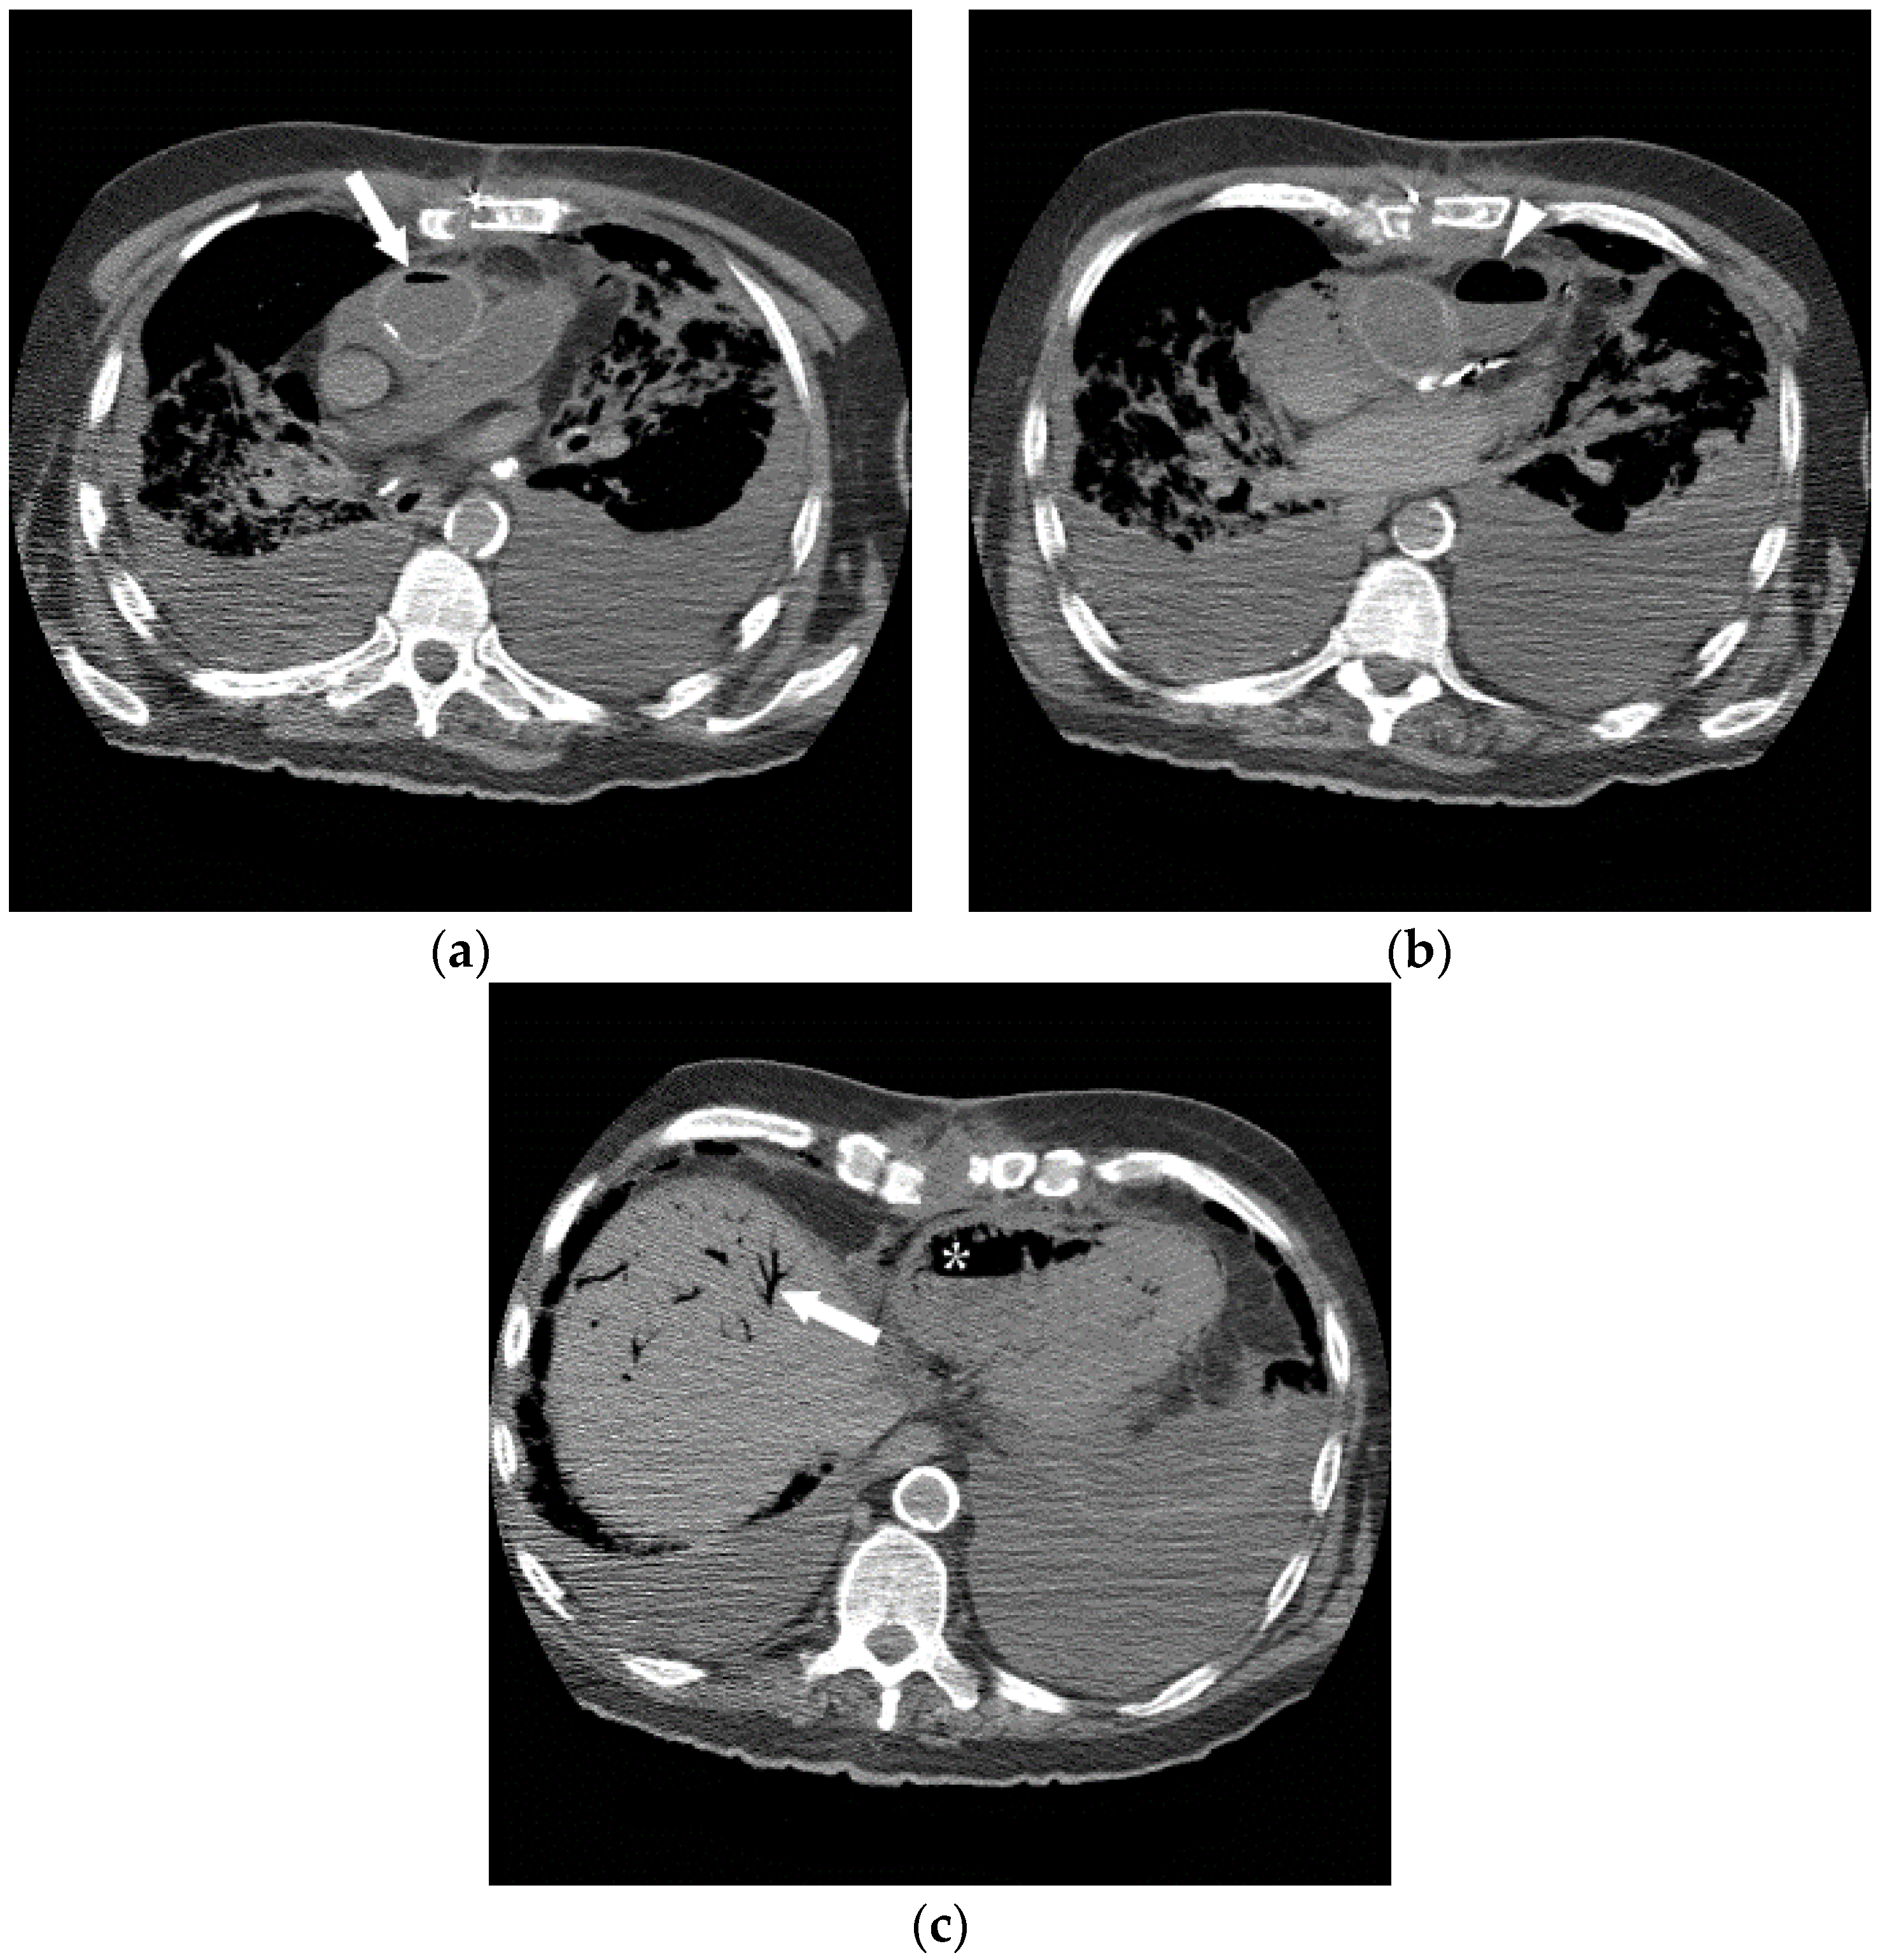

Figure 10.

The successful use of a hyperbaric oxygen therapy (HBOT) is outlined in this case, in which a 69-year-old female with a history of suspected lung cancer underwent a CT-guided lung biopsy at an outside facility (a). During the procedure, the patient suffered a cardiorespiratory arrest. An immediate CT (b) revealed a right pneumothorax (arrow), together with air in the right pulmonary vein (arrowhead). Additional images from the CT scan (c,d), revealed air in the right coronary artery (black arrow), the ascending thoracic aorta (white arrow) and the epidural veins (arrowhead). The patient was initially unresponsive and required cardiopulmonary resuscitation. A non-contrast CT brain (e) was performed, revealing air scattered in the vessels overlying the right cerebral hemisphere (arrowheads). Subsequent MRI of the brain confirmed multiple areas of acute infarction in the right cerebral and cerebellar hemispheres. Axial T2 (f) and DWI (g) images of the brain demonstrated acute areas of infarction in the right cerebellum. The patient required ICU management and HBOT.